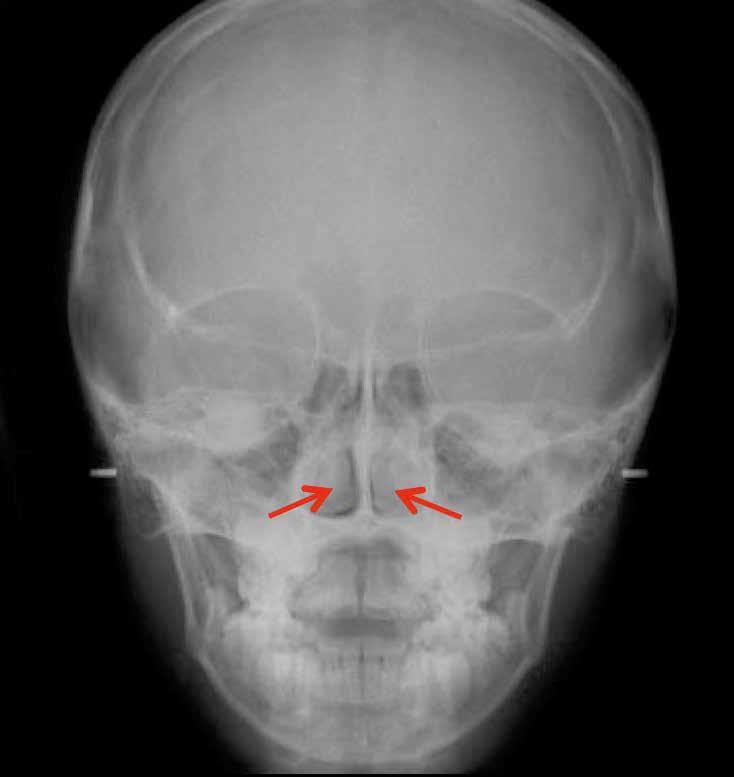

A 10 éves férfi páciens a felső frontfogai késői/nem megvalósuló előtörése miatt kereste fel a rendelőnket. A klinikai és a radiológiai vizsgálat során a jobb felső nagymetszőfog impakcióját észleltük (1. ábra). A fog horizontális tengelyállással és dilacerált gyökérrel rendelkezett. A felső dentális középvonal a fogak vándorlása miatt jelentős mértékben elcsúszott. A bal felső kismetszőfog is rendkívül kedvezőtlen pozícióba került.

1. b ábra: A panoráma röntgenfelvételen megfigyelhető a teljes impakcióban lévő jobb felső nagymetszőfog. 1. c ábra: A CBCT felvétel is igazolja a jobb felső nagymetszőfog impakcióját.